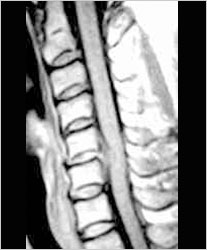

MRI造影中颈椎C5/6处可见明显的椎间盘突出

术后MRI造影中颈椎C5/6突出椎间盘消失的无影无踪